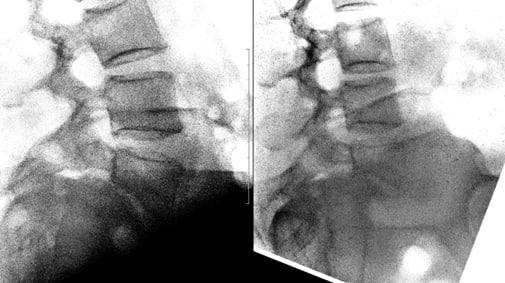

Пациент делает рентгеновские снимки не просто стоя, а в максимальном наклоне вперед и назад. Это показывает, как ведут себя позвонки в движении. Смещение, которое было незаметно в статике (на МРТ или КТ), может явно проявиться при сгибании-разгибании.

Бывает, что спондилолистез, четко видимый на МРТ, оказывается стабильным на функциональных снимках — то есть позвонки не «ездят» друг относительно друга при движении. И наоборот, вроде бы небольшая проблема на МРТ может маскировать серьезную нестабильность.